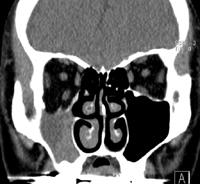

CT

右片側性上顎洞炎

右上顎洞の虚脱

uncinate processの外側への偏位

中鼻道の拡大

眼窩下壁の尾側への偏位;眼窩容積の増大

後方の側頭下窩脂肪の増生

CT冠状断像軟部濃度条件表示